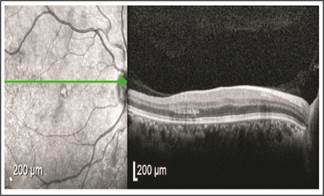

Fig. 7: Juvenile X- linked Retinoschisis. Intraretinal split at the fovea

Fig. 8: Retinal Arteritis Right eye OCT and corresponding FFA. The left eye was normal.

06 years old male child was included. The visual acuity was 6/24 in both eyes with no significant refractive error and a subtle yet undiagnosed maculopathy. On OCT both eyes were showing a similar picture (figure. 08). These findings were consistent with Juvenile X-linked Retinoschisis.

Differential diagnosis included cystoid macular edema associated with Retinitis Pigmentosa.16 Important to note is that both these conditions are angiographically silent (show no leakage on FFA). Incidence of JXLR is estimated at 1:5000. These features have been discovered on OCT by other investigators who also state their presence in an apparently normal fundus.17